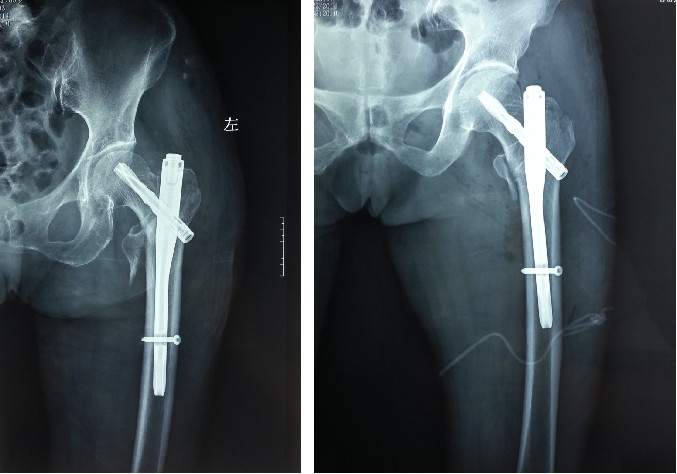

Меньший диаметр гвоздя (обычно 9 мм) можно вбить без расширения.(выше более толстого каудального конца стержня Gamma - 17 мм)

Проксимальный конец PFN имеет изгиб приблизительно 6 градусов, что уменьшает угол вальгуса и устраняет необходимость сильной внутренней ретракции во время тракции.

Верхний конец позволяет установить два винта в головку бедренной кости с добавлением винта, препятствующего ротации, и двойного стержня в шейке бедренной кости, что увеличивает сопротивление усталости.

Расстояние между дистальным фиксирующим отверстием и дистальным концом основного стержня (коническое удлинение) больше, что может снизить концентрацию напряжения в бедренном стержне.

Относительно меньше травм.

Это малоинвазивный метод интрамедуллярной фиксации с небольшим разрезом и минимальной травмой.

Гвоздь Gamma прочно соединяет верхнюю часть бедра и шейку бедра за счет комбинации интрамедуллярного стержня и натяжного винта, а интрамедуллярный стержень фиксируется дистальным самоблокирующимся стержнем, что предотвращает ротацию и укорочение смещения и обеспечивает надежную фиксацию.

Идеально подходит для нестабильных межвертельных переломов бедренной кости.

Он прочно фиксирует головку и шейку бедренной кости и предотвращает вращение конца перелома.

Предотвращает такие осложнения, как коллапс из-за резорбции кости после потери медиальной опоры, инверсионной деформации и вырезания головки бедренной кости вкладышем.

Подходит почти для всех межвертельных переломов, особенно для нестабильных переломов (например, передние межвертельные переломы) и комбинированного остеопороза.